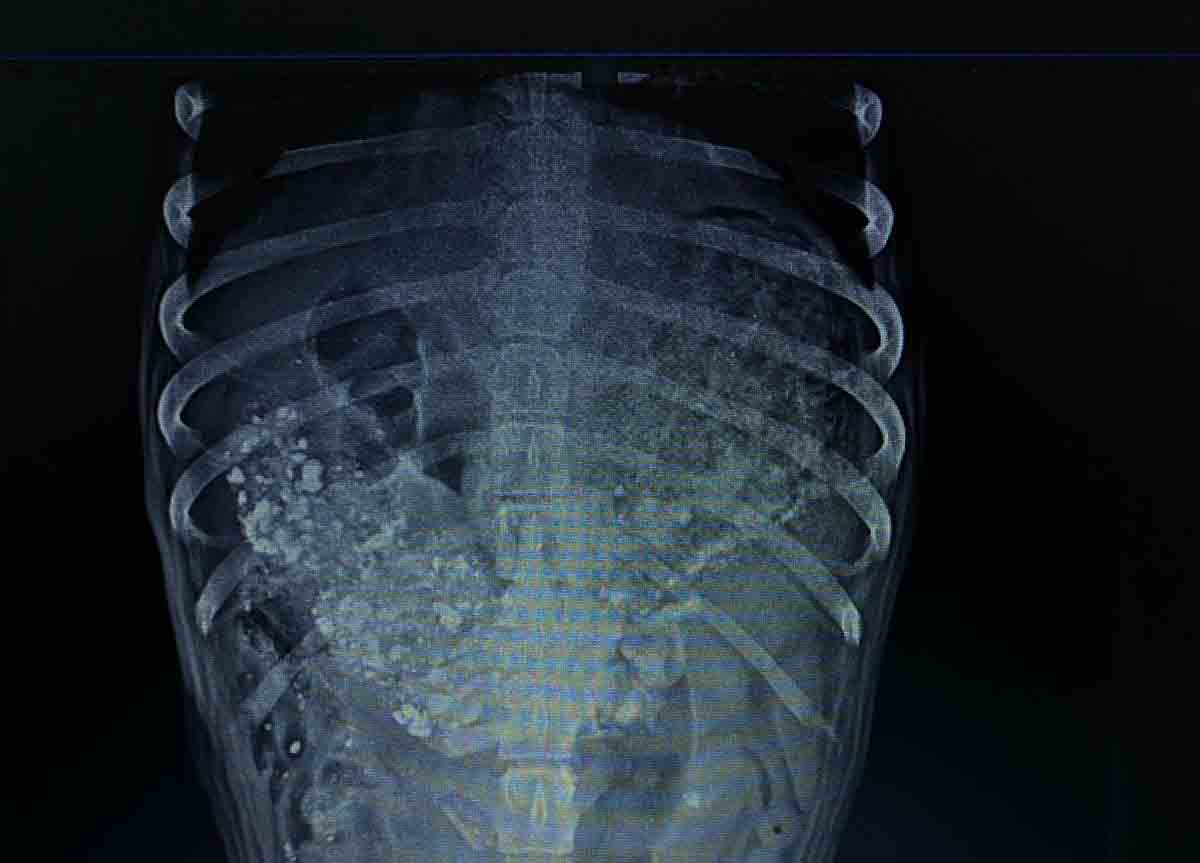

Com fome, um dos animais tinha pedras no estômago, conforme constatado em exame de raio-X

Após a denúncia, a Polícia Militar (PM) acompanhou o resgate e garantiu a segurança da operação e a retirada do animal do local. Ele foi levado ao

Hospital Veterinário Popular (UPA PET) e, após exames, foi diagnosticado que havia ingerido pedras.